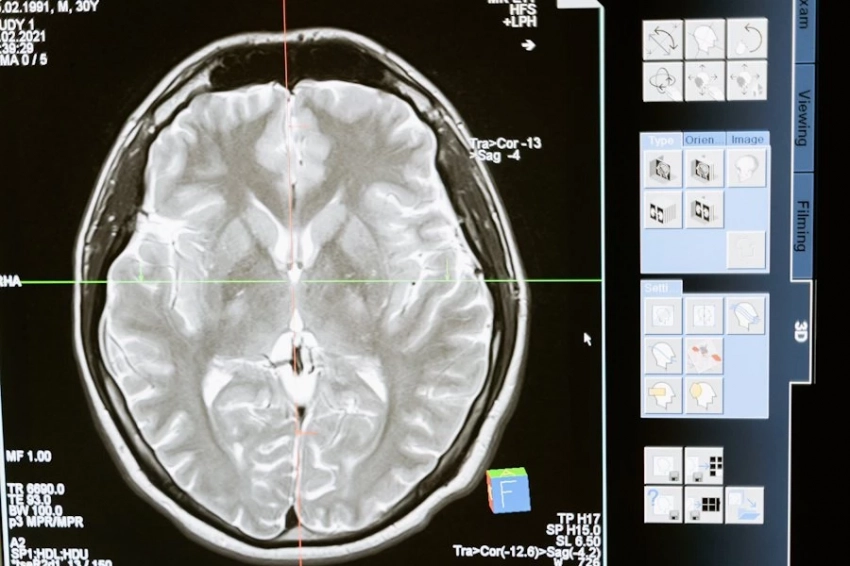

Согласно порталу npj Science of Food, для оценки влияния зеленого чая и кофе на здоровье мозга использовались данные анкет по частоте употребления напитков, а также результаты магнитно-резонансной томографии (МРТ). Анализ показал, что у людей, которые пили больше зеленого чая, реже наблюдались поражения белого вещества мозга — ключевого компонента, отвечающего за передачу сигналов между различными отделами мозга. Однако на объем гиппокампа — структуры, связанной с памятью, и общий объем мозга потребление зеленого чая заметного влияния не оказало.